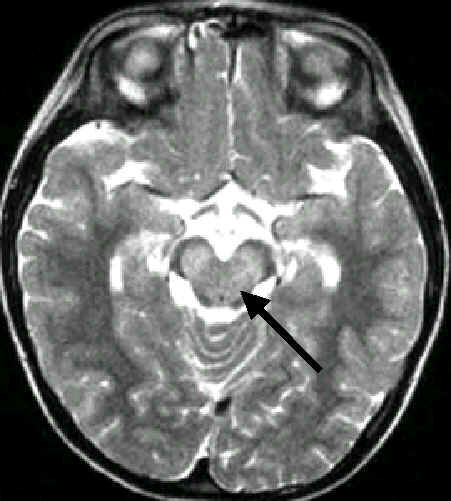

4歲男孩,手足口疾病合併腦炎

腦炎侵犯

中腦的中央

(箭頭所指變亮之處)